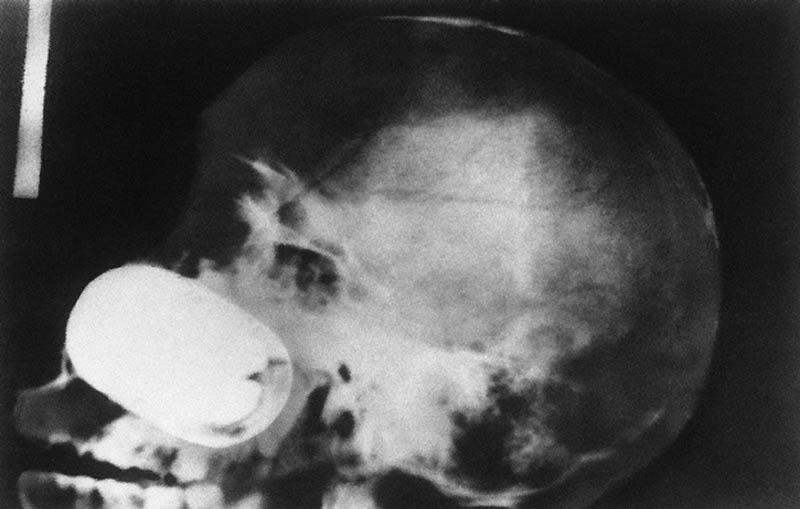

Гвоздь в человеческом черепе – пациент случайно выстрелил в себя из пневматического молотка. Он даже не понял, что выстрелил в себя – 10-сантиметровый гвоздь обнаружили только через 6 дней